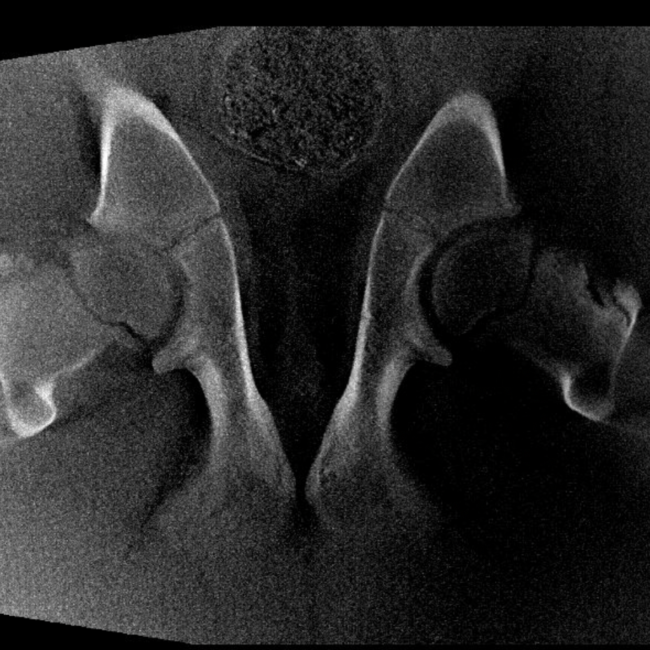

Our High Definition Volumetric Imaging (HDVI) technology represents the most advanced stage of Flat Panel CT technology. It offers exceptional diagnostic imaging for both hard and soft tissues, in diagnostic settings and intraoperative theaters. It is the gold standard for orthopedic applications.

Pegaso enhances safety and usability by enabling the scanning of a standing horse’s head, neck, and limbs.

Pegaso scans head, neck and limbs of the standing horse